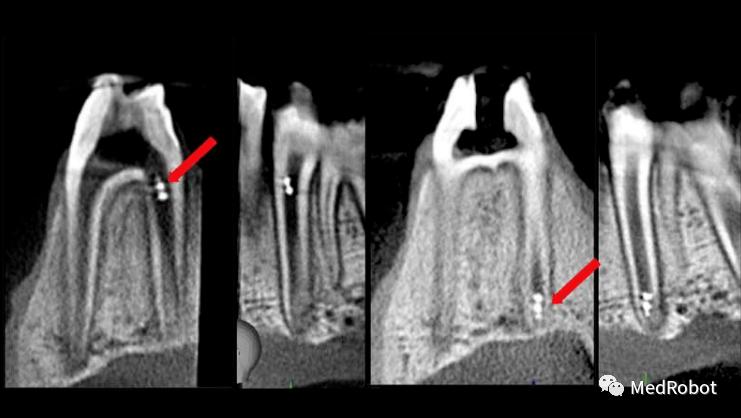

▲红色箭头所指示的磁制动3D微型机器人被精确控制,

以达到根管的顶端区域

(图源:宾夕法尼亚大学)

此外,研究小组展示了使用现有的成像技术(如口内扫描仪,牙科X射线和锥形束计算机断层扫描)实时跟踪微型机器人的独特能力,这些技术能够在完整的牙管中定位螺旋体。